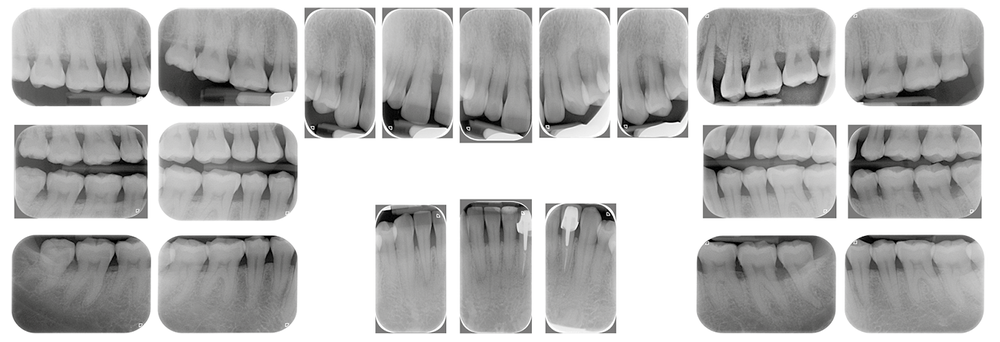

À l’examen clinique et radiologique, elle présente une parodontite de stade 4 grade C avec des poches profondes au niveau des dents 11 et 24, associées à des alvéolyses angulaires atteignant la moitié ou les deux tiers de la hauteur radiculaire au niveau du secteur incisivo-canin maxillaire, et le quart de la longueur radiculaire des premières molaires maxillaires et mandibulaires (fig. 2).